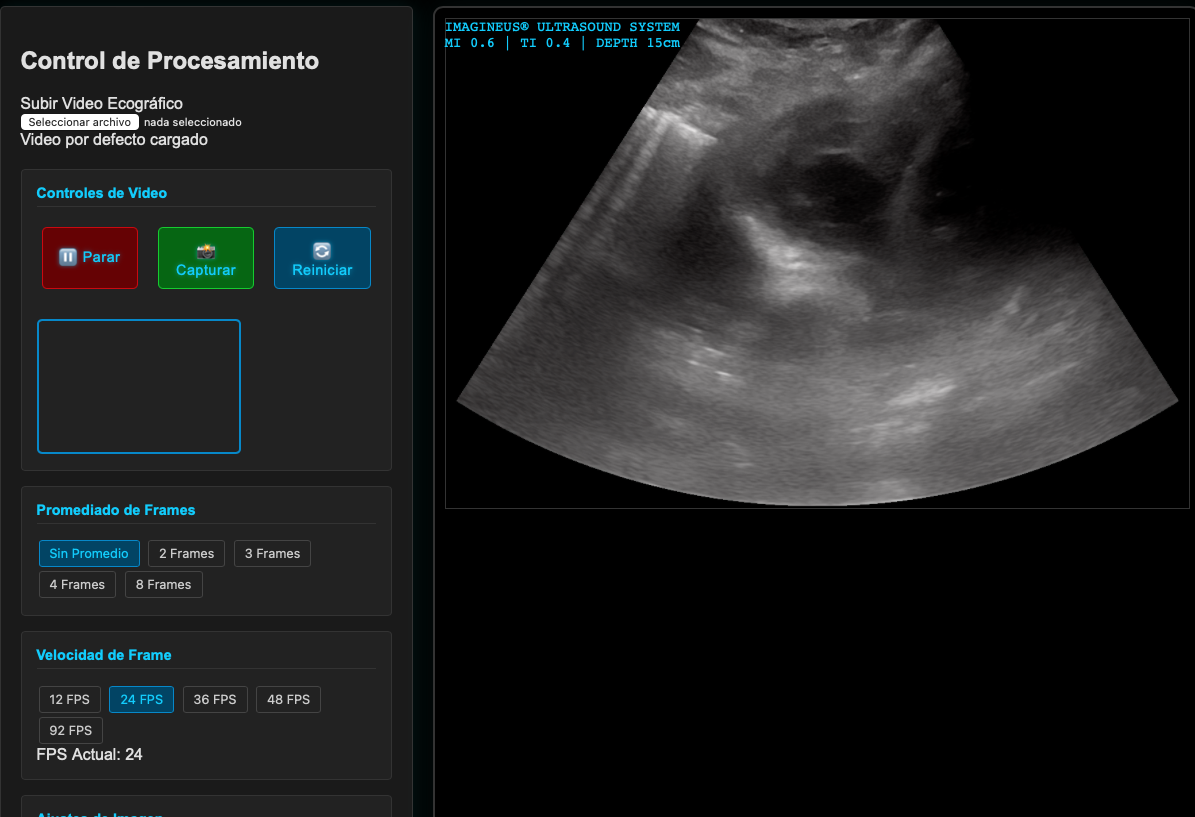

Postproceso en Ecografía

El postproceso en ecografía se refiere a los pasos que se realizan después de capturar las imágenes o videos para optimizar la interpretación y el uso clínico de los datos obtenidos. Esta etapa incluye ajustes, almacenamiento, análisis y generación de informes, permitiendo una mejor documentación y comprensión de los hallazgos ecográficos.

Captura de Imágenes

La captura de imágenes consiste en guardar fotogramas seleccionados durante el estudio ecográfico. Estas imágenes suelen elegirse para resaltar las características anatómicas o patológicas más relevantes. Por ejemplo, al evaluar un quiste ovárico, el operador capturará las vistas que muestren su tamaño, contorno y relación con estructuras adyacentes.

Video

La grabación de video en ecografía permite documentar secuencias en tiempo real, como el movimiento del corazón o el flujo sanguíneo en un vaso. Esto es especialmente útil en estudios dinámicos, como los realizados con Doppler color, donde las imágenes fijas no capturan adecuadamente la funcionalidad o el patrón de flujo observado.

Zoom

El zoom permite ampliar una sección específica de la imagen para observar detalles con mayor precisión. Es especialmente útil para estudiar zonas pequeñas o anomalías específicas, permitiendo un análisis detallado sin perder el contexto general de la imagen.

Compensación de Ganancia por Tiempo (TGC)

La compensación de ganancia por tiempo (TGC) ajusta la ganancia de forma independiente a diferentes profundidades, ayudando a mejorar la uniformidad de la imagen al corregir la atenuación del ultrasonido en tejidos más profundos. Esto garantiza una visualización clara tanto de las estructuras superficiales como profundas, optimizando la calidad de la imagen.

Explora más sobre TGC en el simulador interactivo.

TGC en ecografía

Imagenus 6: Ejemplo de ajuste de TGC en ecografía para mejorar la imagen en profundidad.